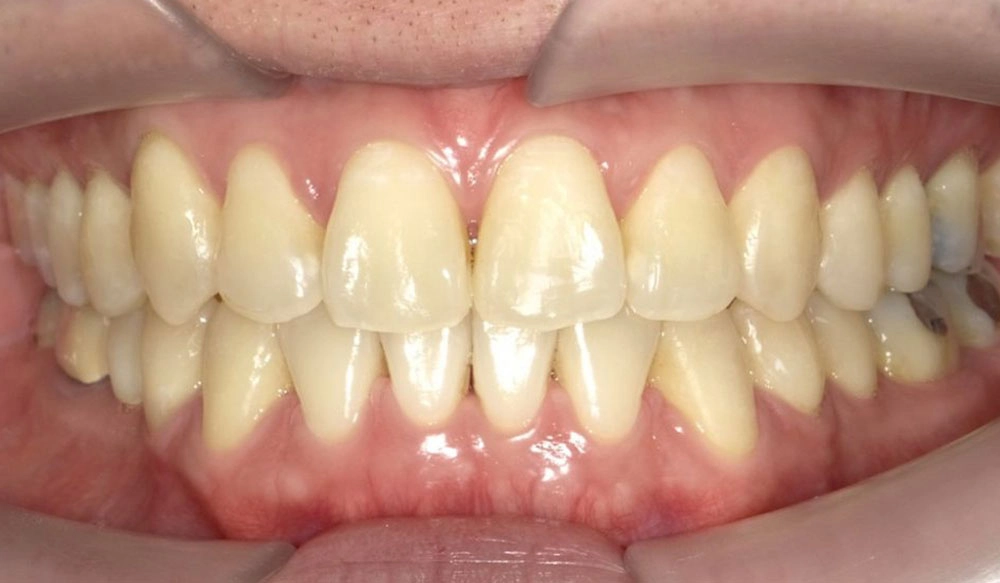

Crowding

Crowding is the condition in which there is a discrepancy between tooth size and space available for the teeth to be aligned in the dental arch

Patient Information:

Age: 17

Gender: female

Invisalign Treatment Option: Invisalign Comprehensive

Total Treatment Time:

29 months